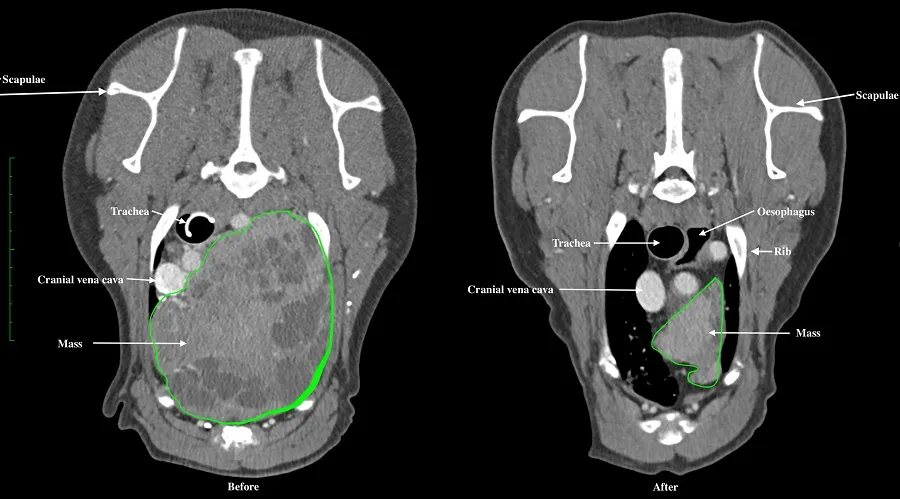

Images before and after treatment show that radiotherapy has reduced the size of Bailey's tumour (outline shown in green) by more than 50 per cent

Bailey received 20 fractions of radiotherapy as an out-patient over a four-week period using the Hospital’s VitalBeam linear accelerator. Cone beam CT was performed on a daily basis to verify patient position, so that treatment could be applied with millimetre accuracy.

Nine months after the final radiotherapy session, Bailey’s tumour continues to get smaller and is now less than 50 per cent of its original size. Bailey’s calcium levels have also remained normal since treatment. Radiotherapy has reduced the size of Bailey’s thymoma by more than 50 per cent.